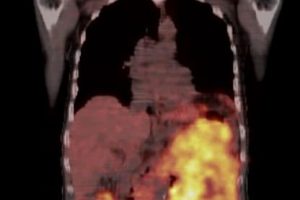

– Vratio sam se iz Turske, s prve kontrole. Prva vijest je da se, nakon samo mjesec dana pametne terapije kancer polako počeo smanjivati. Prva bitka je dobijena, ali rat protiv napasnika, koji je veoma velik, i dalje traje, do pobjede, istakao je.

– Ovim putem želim zahvaliti svima koji su pomogli da odem do Turske i započnem uspješno liječenje. Nakon prvobitnih najava da je bitka izgubljena unaprijed, preko procjene turskih ljekara da su šanse 50-50, do pozitivnih vijesti s prve terapije. Ja se nastavljam boriti DO KONAČNE POBJEDE, napisao je Safet uz fotografije iz Turske.